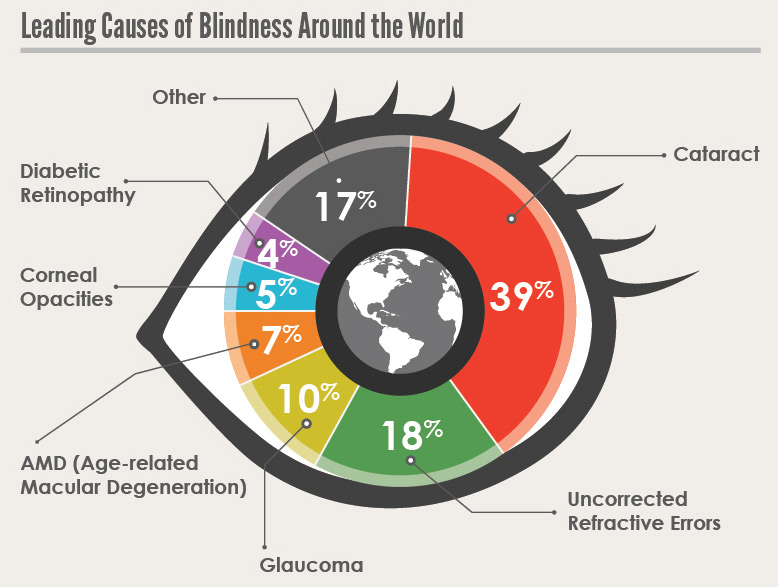

La Ceguera por cataratas afecta a millones de personas en todo el mundo y sigue siendo la principal causa de ceguera en todo el mundo. A pesar del uso generalizado de la facoemulsificación en el mundo desarrollado, aproximadamente 20 millones de personas son ciegas debido a cataratas bilaterales, principalmente en el tercer mundo. Recientemente ha sido publicada una Revisión de la literatura en la revista Current Opinion in Ophthalmology elaborada por Cameron Lee y Natalie Afshari del Shiley Eye Institute, UC San Diego, California (USA).

Los últimos estudios han encontrado que el número de ciegos debido a la catarata en todo el mundo pasó de 12,3 millones en 1990 a 20 millones en 2010. La proporción de ceguera por cataratas oscila entre el 12,7% en América del Norte y el 42,0% en el sudeste asiático. La mayor prevalencia de ceguera estandarizada por edad en adultos mayores de 50 años se encuentra en el África subsahariana, con una tasa del 6,0% en el África subsahariana occidental y una tasa del 5,7% en el África subsahariana oriental.

El África subsahariana continúa siendo un área particularmente notable en cuanto a la ceguera de la catarata. La catarata fue la principal causa de ceguera en todos los países de África subsahariana, excepto en dos países distintos de Camerún y Uganda. La menor disminución de la ceguera a causa de cataratas en todo el mundo fue en el este de África subsahariana, una región que incluye a Tanzania, que tenía una tasa de ceguera del 67% debido a cataratas.